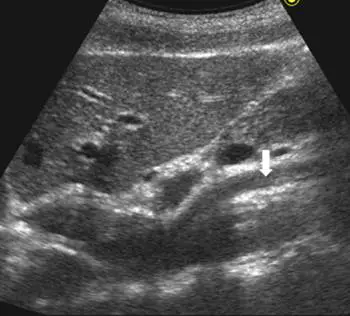

附圖為上腹部超音波影像,箭號所指的低回音構造為下列何者?

- 切面與相對位置:此為上腹部的縱切面(Longitudinal view)超音波影像。影像最上方(靠近探頭接觸的腹側)為肝臟左葉(Left lobe of liver)。

- 腹主動脈(Abdominal Aorta):在肝臟下方較深處,可見一條粗大的、呈現水平走向的無回音/低回音管狀構造,此即為腹主動脈。

- 主動脈的兩個前分支:

- 第一個分支(靠近頭端,畫面偏左):為腹腔動脈幹(Celiac trunk),其特徵為從腹主動脈前壁發出後,會較快產生分叉(分為肝總動脈與脾動脈),走向不與主動脈平行。

- 第二個分支(靠近尾端,畫面偏右):即為白色箭號所指的構造。它位於腹腔動脈幹下方約 1 公分處,其最顯著的影像特徵是起源後會向尾端延伸,並與腹主動脈呈現平行的走向。這個管狀構造就是上腸繫膜動脈(Superior mesenteric artery, SMA)。

- (B) 上腸繫膜動脈(superior mesenteric artery):SMA 是腹主動脈第二個前壁主要分支,其經典超音波特徵便是與主動脈平行走向,圖中白色箭頭明確指向此血管,完全符合 SMA 的解剖表現,為正確答案。

綜合上述影像特徵,圖中顯示的是標準的腹主動脈縱切面超音波影像。根據解剖位置,從腹主動脈前壁發出且與主動脈平行走向的第二條主要分支血管,毫無疑問是上腸繫膜動脈(Superior mesenteric artery),因此正確答案為 (B)。